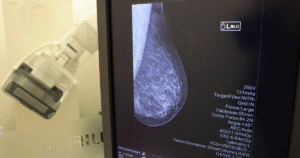

Hospitalito Fomenta la Detección Temprana del Cáncer de Mama

El Hospitalito se une al Mes Rosa para promulgar la autoexploración y la revisión médica periódica con el objetivo de detectar el cáncer de mama en una fase temprana.

Del 6 al 31 de octubre ofrecerá un paquete de mastografía, ultrasonido de mama y consulta con un especialista de clínica con un precio especial de 500 pesos.

“A partir de los 40 años hasta los 65 años se debe realizar una exploración clínica por un médico especialistas acompañada por exploración por mamografía y ultrasonido mamario. Antes de esta edad se puede realizar un ultrasonido mamario o bien la autoexploración de cada paciente, esto con el fin de identificar datos de alarma o alguna lesión que nos pudiera condicionar eventualmente cáncer de mama. La importancia de hacerlo año con año es la identificación temprana y el seguimiento de estas lesiones”, detalló la ginecóloga del Hospitalito, Goretti Hernández Martínez.